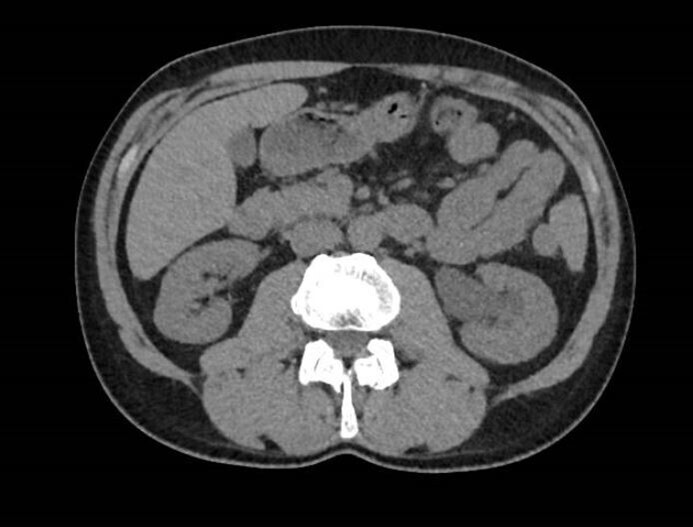

Voici les images clés du scanner réalisé (figures 1 et 2) : Figure 1 (Source : Théo Arber, La Revue du Praticien)

Figure 2 (Source : Théo Arber, La Revue du Praticien) Il n'y a pas d'abcès rénal.